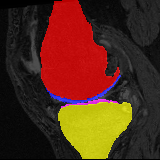

Moving Target Mono-0 Mono-5 DA-1 DA-5 Mono-200 Refer to caption Refer to caption Refer to caption Refer to caption Refer to caption Refer to caption Refer to caption Refer to caption Refer to caption Refer to caption Refer to caption Refer to caption Refer to caption Refer to caption

Figure 2:  Examples of knee MRI registration (top) and brain MRI segmentation (bottom) results. Top: The first two columns are the moving image/segmentation and the target image/segmentation followed by the warped moving images (with deformation grids)/segmentations by different models. Bottom left to right: original image, manual segmentation, and predictions of various models. Mono-i𝑖i and DA-i𝑖i represent the mono- and DA models with i𝑖i manual segmentations respectively.

Results: All trained networks are evaluated using Dice overlap scores between predictions and the manual segmentations for the segmentation network, or between the warped moving segmentations and the target segmentations for the registration network. Tabs. 1 and 2 show results for the knee and brain MRI experiments respectively in Dice scores (%). Fig. 2 shows examples of knee MRI registrations and brain MRI segmentations.

Knee results: On knee MRIs, our method improves segmentation scores over separately learned networks by about 1.2 and 0.5, and registration scores increase by about 3.1 and 3.0, when training with 5 and 10 manual segmentation respectively. Especially for the challenging cartilage structures, our joint learning boosts segmentation by 1.4 and 0.7, and registration by 5.5 and 5.2 for N=5 and N=10 respectively.

Qualitative results: DA achieves more anatomically consistent registrations than the mono-networks on the knee (Fig. 2) and Brain MRI samples (see supplementary material).

Moving Target Mono-0 Mono-21 DA-1 DA-21 Mono-65 Refer to caption Refer to caption Refer to caption Refer to caption Refer to caption Refer to caption Refer to caption Refer to caption Refer to caption Refer to caption Refer to caption Refer to caption Refer to caption Refer to caption

Figure 4: Examples of brain MRI registration (top) and knee MRI segmentation (bottom) results. Top: The first two columns are the moving image/segmentation and the target image/segmentation followed by the warped moving images/segmentations by different models. Bottom left to right: original image, manual segmentation, and predictions of various models. Mono-i𝑖i and DA-i𝑖i represent the mono- and DA models trained with i𝑖i manual segmentations respectively.